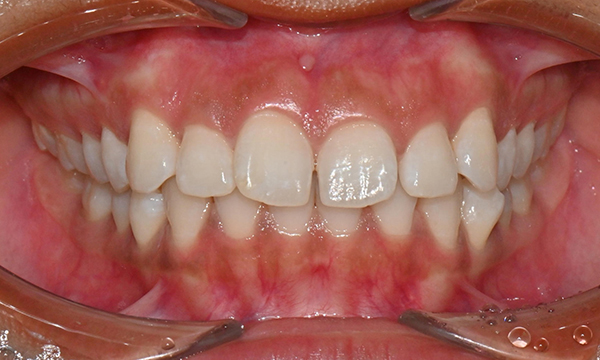

치아 상태는 어땠냐면요:

위아래 앞니 사이에 공간이 벌어져 있었어요.

앞니가 삐뚤빼뚤한 덧니도 있었죠.

윗니와 아랫니가 너무 깊게 맞물리는

과개교합이 있었어요.

왼쪽 아래 작은어금니가 90도 돌아가 있었는데,

이로 인해 왼쪽 치아 배열과 교합이 좋지 않았죠.

초진시 구내사진 (2025. 3.31)